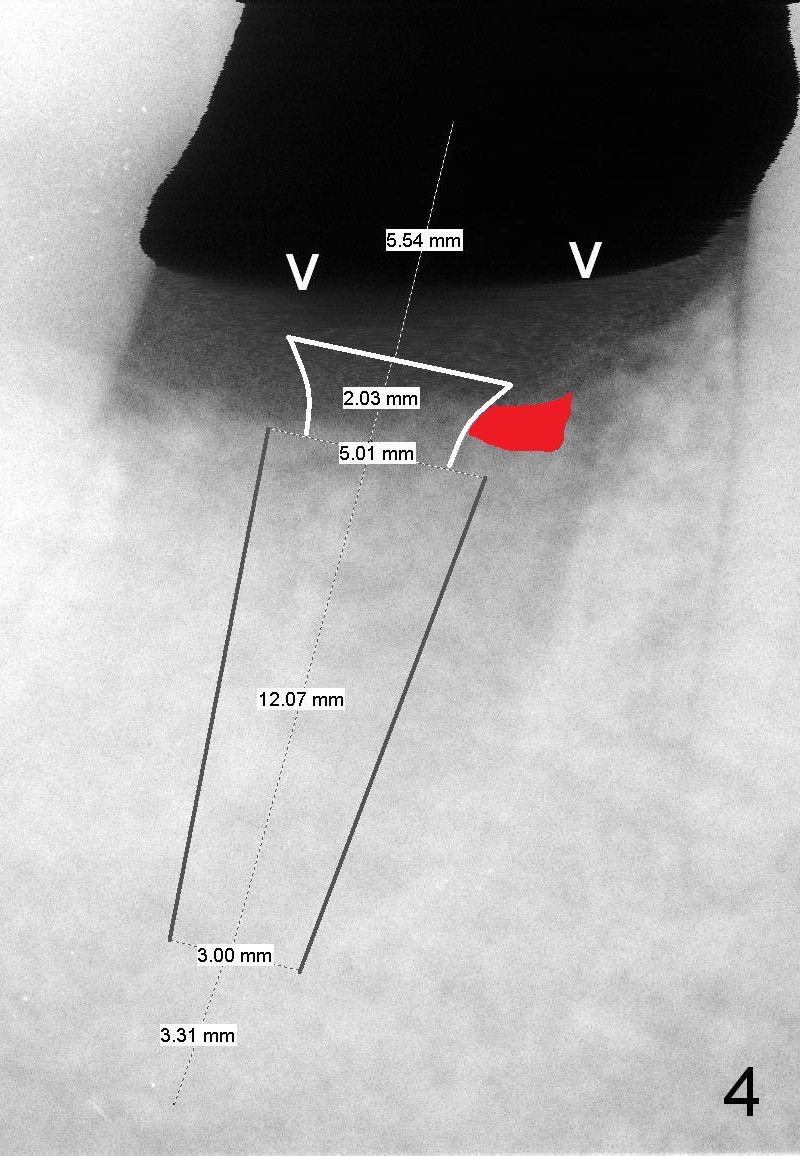

A 44-year-old man lost the tooth #30 three months ago. He is very nervous about the Inferior Alveolar Nerve (Fig.1,3 yellow dashed line). Offer Valium if needed. Check whether there is DO caries of the tooth #29 (Fig.2 <). Finish composite if indicated. There is mild to moderate buccal plate atrophy. The implant may have to be placed slightly lingually. When the insertion torque is high, place an abutment (Fig.3 white inverted cup) with subgingival margin (arrowheads: gingival margin) so that the emergency profile of the crown is better. Make an ideal immediate provisional with good emergency profile and place sutures. The mesial bone may have to be trimmed (Fig.4 red area) so that the abutment is able to be seated without interference. Take photo at each step.